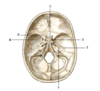

What is A?

Parietal bone

What is B?

Sagittal suture

What is C?

Coronal suture

What is D?

Frontal bone

What is E?

Nasal bone

What is F?

Sphenoid bone

What is G?

Temporal bone

What is H?

Occipital bone

What is I?

Lambdoid suture

What does the sagittal suture connect?

Left and right parietal bone

What does the coronal suture connect?

Left/right parietal and frontal bone

What does the lambdoid suture connect?

Left/right parietal and occipital bone